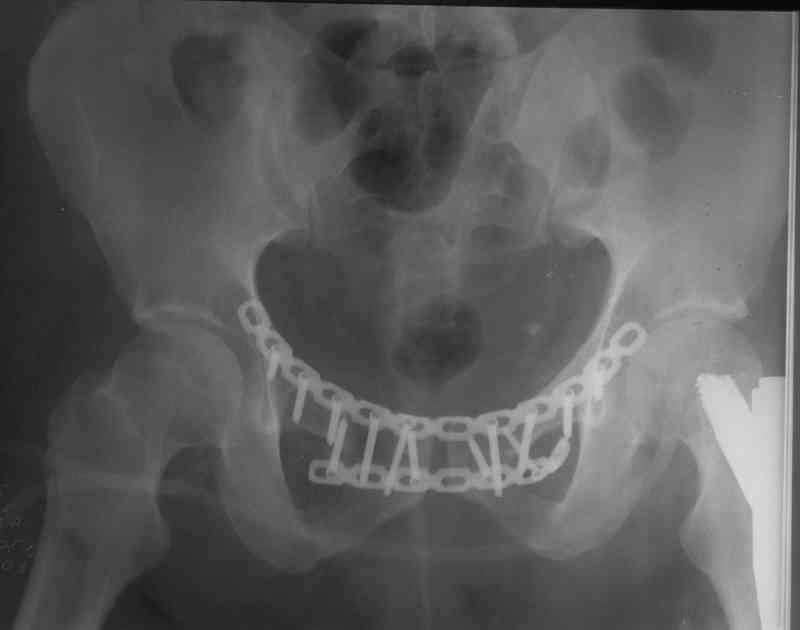

В приложении отправляю послеопер. снимки бедра и лодыжки обсуждаемого вчера больного.

В приложении послеоперационные картинки.